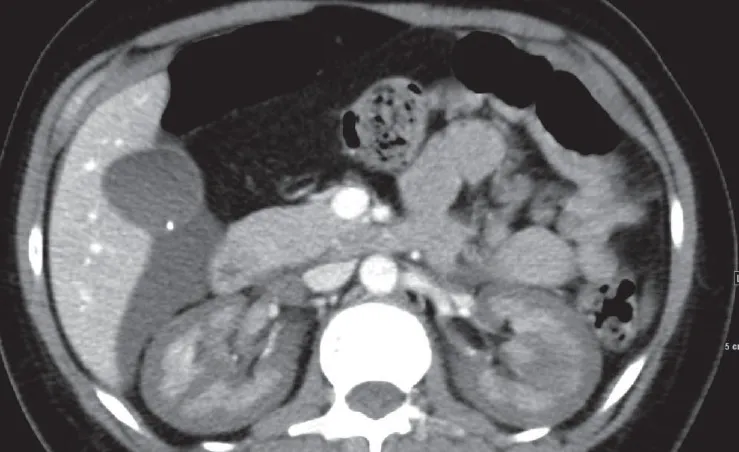

Nos dias seguintes, a creatinina sérica aumentou para 13 mg/dl, acompanhada de anúria. Realizado tomografia computadorizada de abdome (imagem da capa do post) que revelou sinais de necrose cortical renal (NCR), sinais de reversão renal (córtex hipodenso quando comparado a medula renal) com presença de um trombo na veia cava inferior e na veia gonadal direita. A paciente iniciou hemodiálise devido aos sintomas urêmicos e permaneceu dependente da diálise por cerca de dois meses. Após seis meses, a creatinina sérica caiu para 2,4 mg/dl, com um clearance de creatinina de 33 ml/min e proteinúria subnefrótica de 300 mg/d. A paciente continuo em tratamento conservador com diuréticos de alça em baixa dose e anticoagulação.

A NCR é uma forma grave e frequentemente irreversível de lesão renal isquêmica, resultante de uma redução prolongada da perfusão arterial renal. Esta condição é geralmente associada à CIVD e apresenta-se com início abrupto de oligúria ou anúria, algumas vezes acompanhada de hematúria macroscópica e dor no flanco. A TC com contraste mostrou a preservação da medula renal e a hipocaptação cortical (rim reverso), confirmando o diagnóstico de NCR.

3. Diagnóstico por Imagem: TC ou ressonância magnética (RM) são os exames de imagem de escolha para o diagnóstico preciso da NCR.